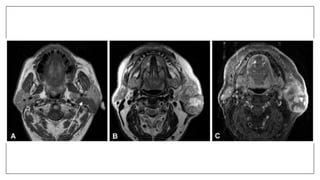

Indications:

• To evaluate the position and integrity of disk inTMJ.

• Evaluating soft tissue disease, especially neoplasia of tongue, cheek,

salivary gland and neck.

• Determining the malignant involvement of lymph nodes.

• Determining perineural invasions.

• Adjunct to ultrasonography in fetal head and neck pathology.

• Visualize edematous changes in fatty marrow and soft tissue in osteomyelitis.

• Localization of mandibular nerve.